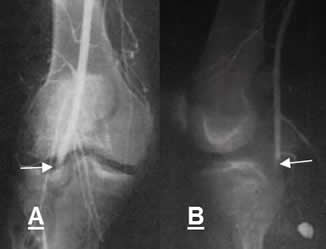

Fig 142 C. Oclusión.

A: Arteriografía AP. Oclusión de la arteria poplítea, después de una luxación de rodilla reducida.

B: Arteriografía lateral. Oclusión de la arteria poplítea, ocasionada por herida con arma de fuego.